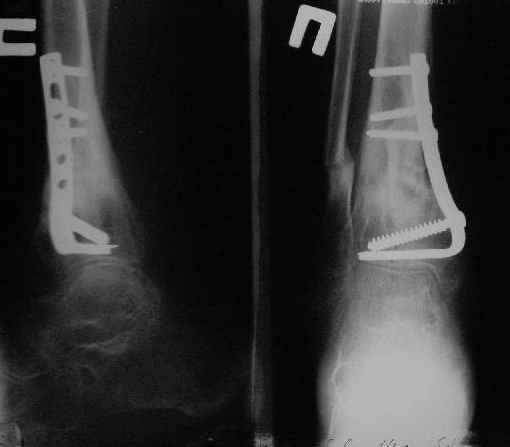

Операции: 1 Клиновидная резекция на вершине деформации м\берцовой кости.

2 Тугоподвижный ложный сустав н\3 б\берцовой кости. Рубцы выполняющие пространство между отломками, канал проксимального отломка иссечены.

Одномоментное устранение деформации, остеосинтез Г-образной пластиной.

Заживление проксимальной части раны вторичным натяжением без нагноения. Рана зажила. Спицы удалены через 1,5 недели после операции.

Учитывая фон (интеллект, etc) гипсовая повязка.

На данный момент ходит при помощи костыля (без присмотра -без костыля :), разрабатывает движения в г\стопном суставе.